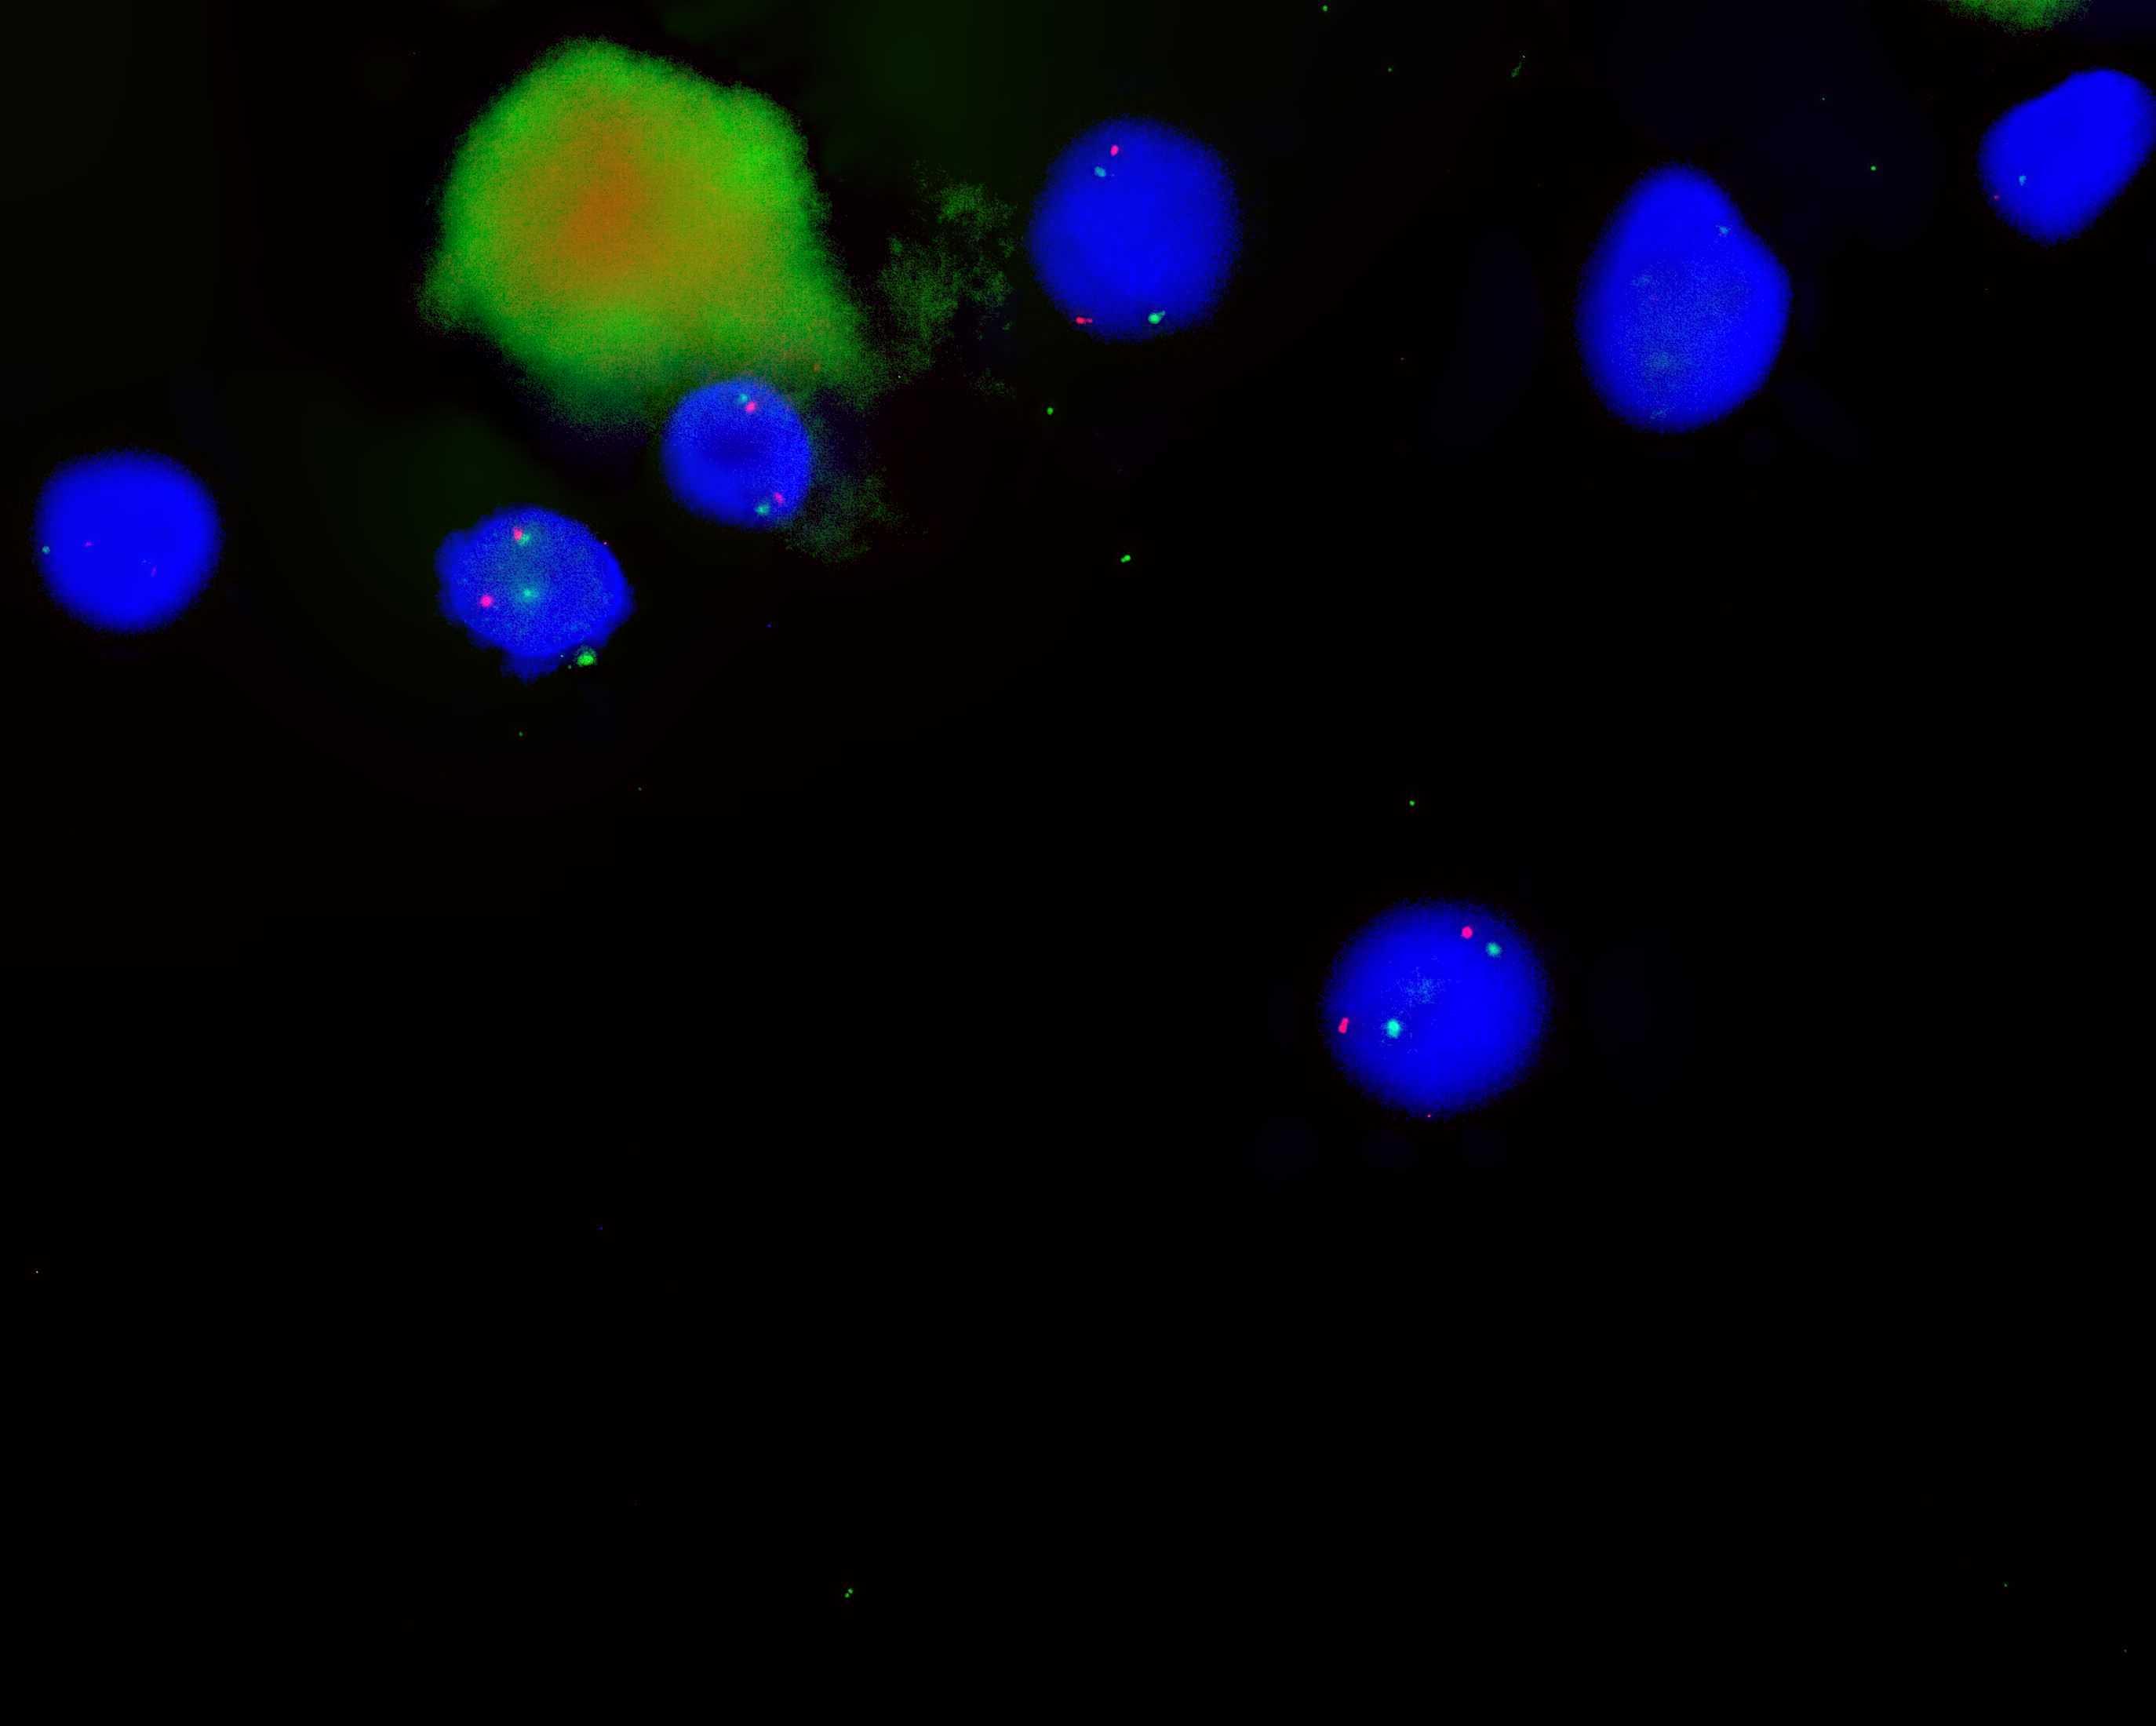

TERC/CEP3 dual color probe

TERC gene (3q26) labeled as orange, with a length of 400 kb; 3 chromosome centromere (CEP3) labeled as green.